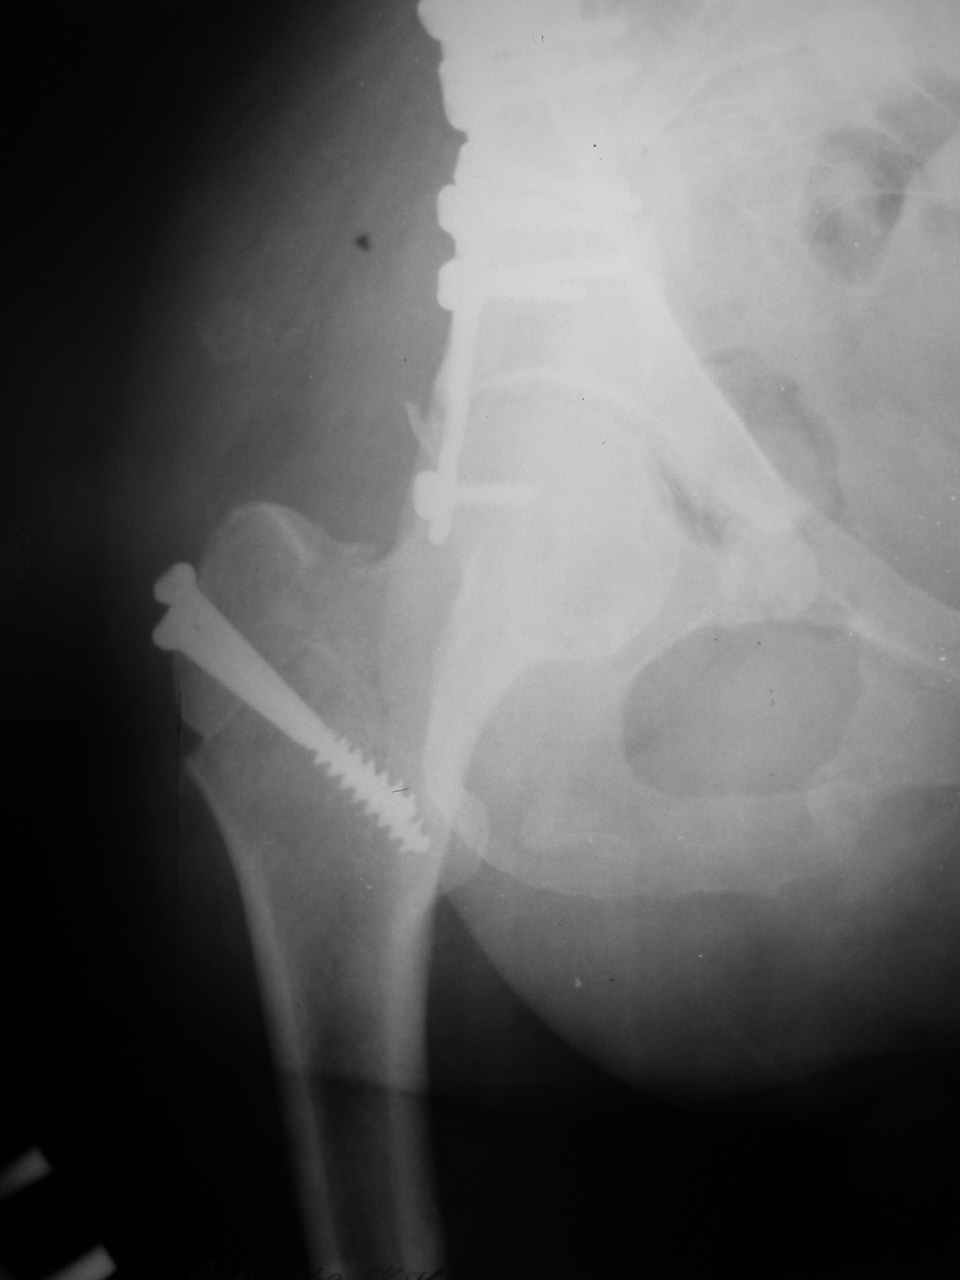

Уважаемые коллеги,43 летний мужчина, попав в автоаварию 13.10.2004, получил оскольчатый перелом обеих колонн левой вертлужной впадины.

На рентгенограммах - высокий двухколонный перелом вертлужной впадины с нарушением конгруэнтности, имеется обратная клиновидность суставной щели.

Спасибо за комментарии и рекомендации. Откровенно говоря, больного я прооперировал на прошлой неделе, через 5 дней после аварии и проблем с ним пока никаких нет, на удивление при достаточно обширной диссекции (илиофеморальный доступ) болей практически нет, так что больной самостоятельно садится в кровати, выполняет активные движения в оперированном суставе, сгибая до 60 градусов пока, далее с ассистенцией.

Причиной обращения к сообществу были возникшие непосредственно после операции сомнения и разочарования полученным качеством репозиции: а надо ли было трогать перелом вообще, репозиция передней колонны технически была очень сложна для меня, хотя реконструкции была в той же последовательности, что Д-р А.В.Рунков рекомендовал, в какой-то момент безуспешных манипуляций стал думать о *вторичной конгруэнтности*, которую не так давно обсуждали на

форуме и скелетном вытяжении. С репозицией и фиксацией задней колонны и отдельно задне-верхней стенки впадины проблем не возникло. Послеоп. Рг граммы в приложении. Если возникнут какие-либо дополнения или поправки - был бы признателен.